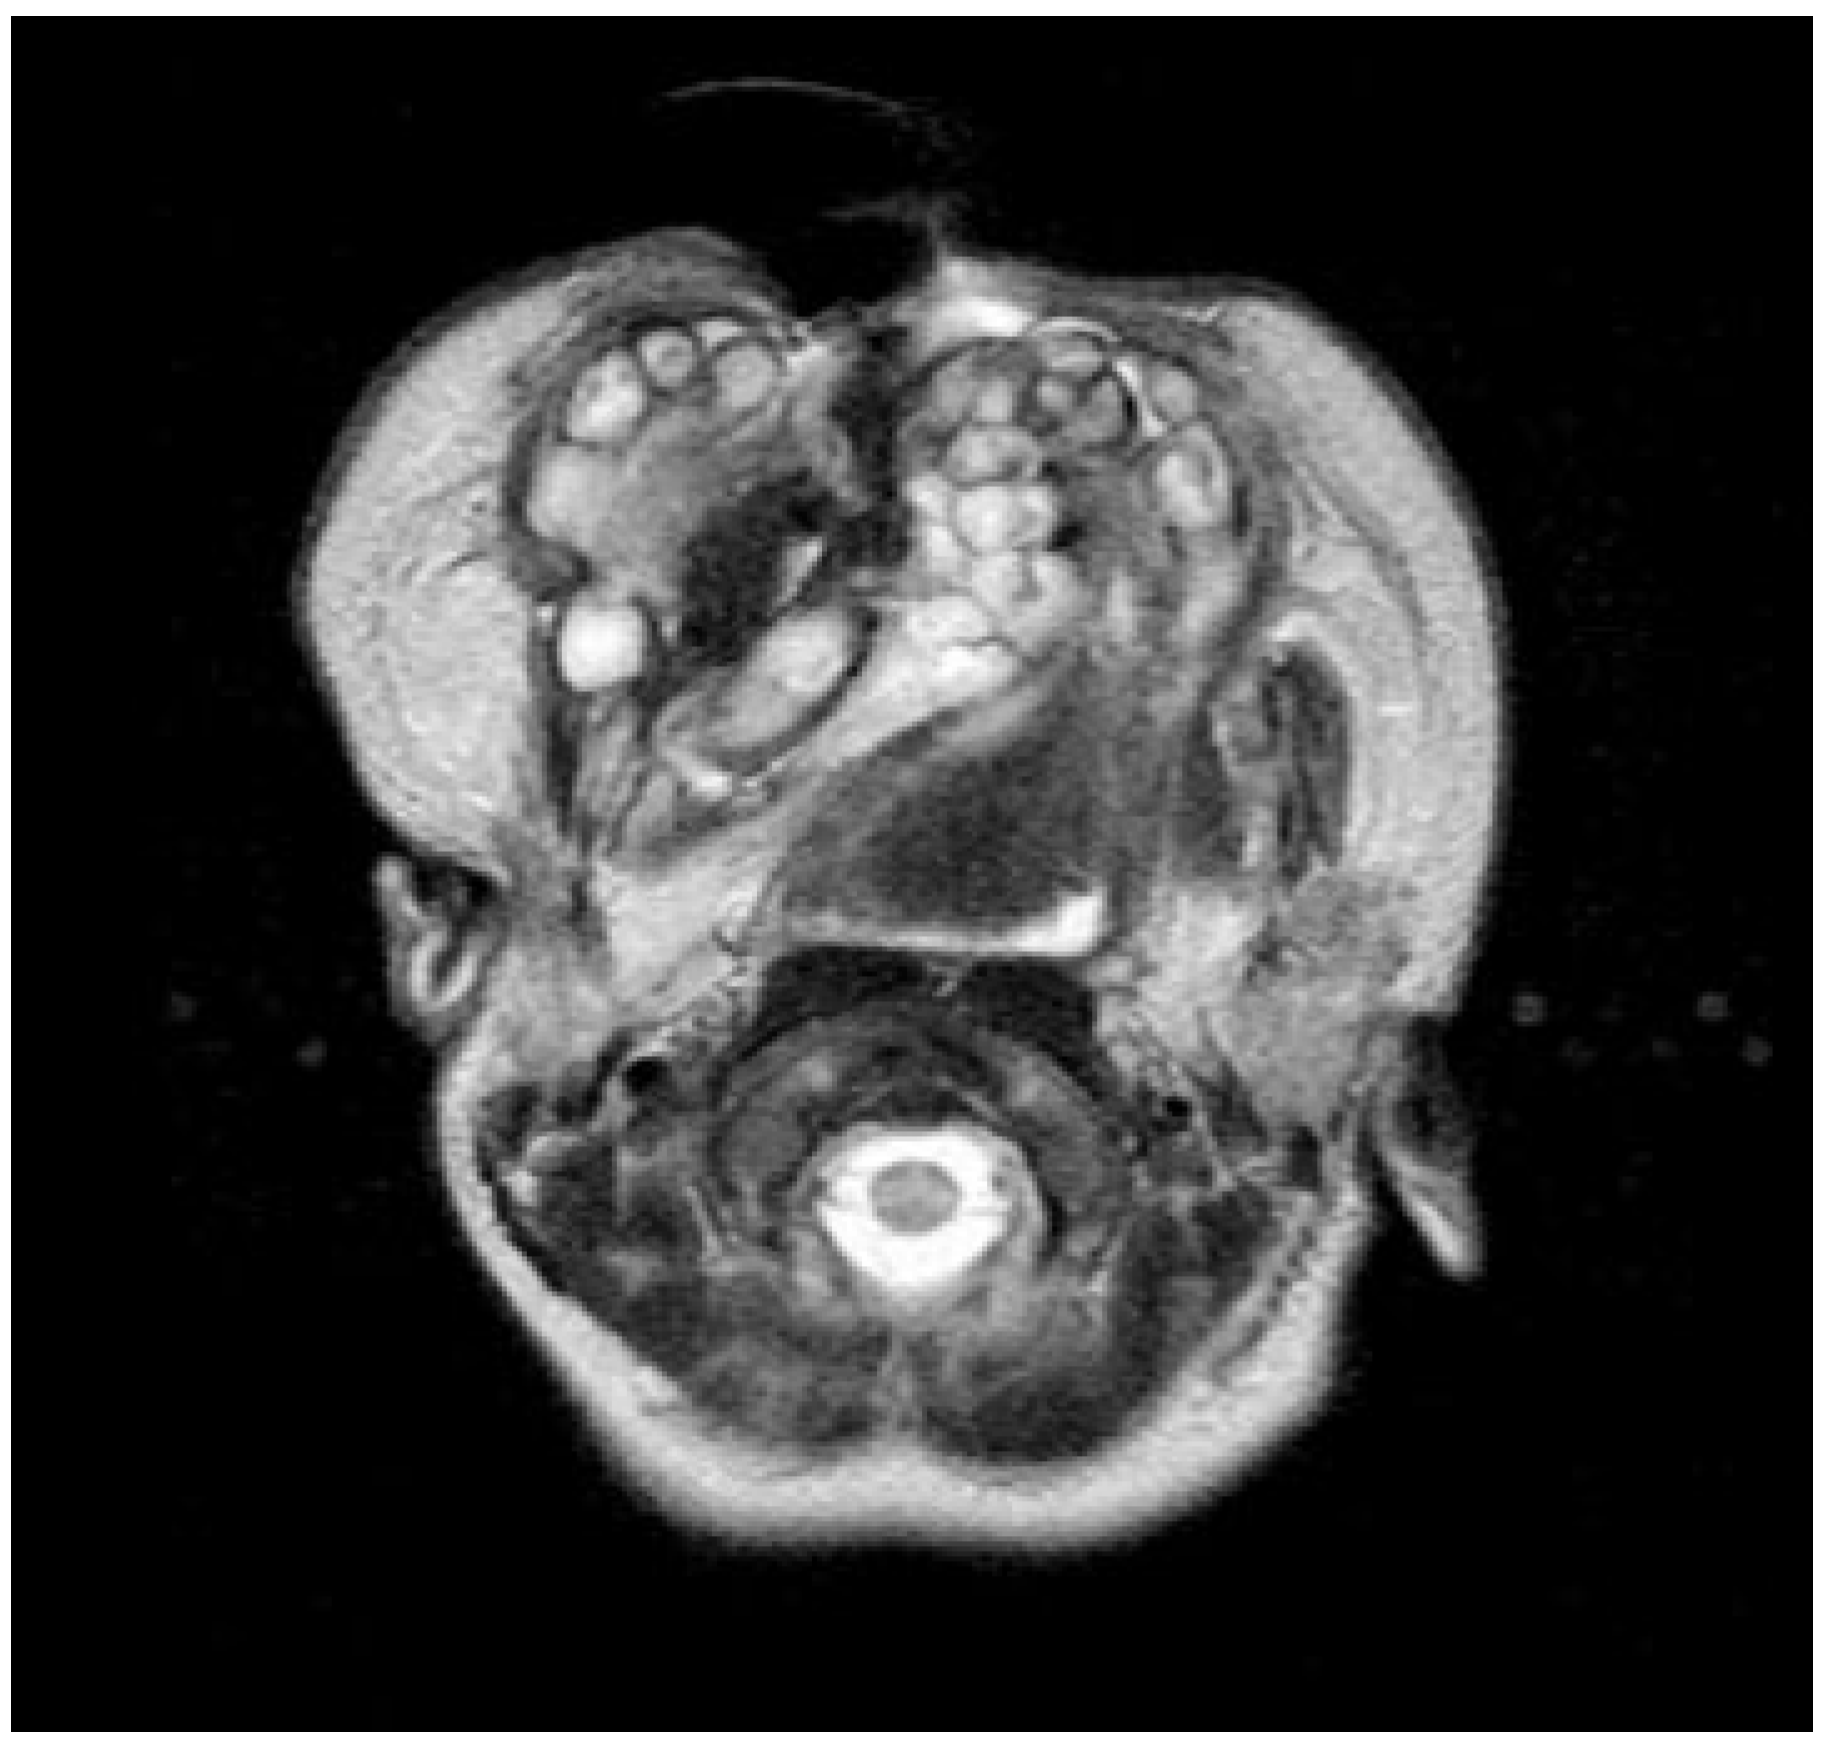

Neonatal examination exhibited frontonasal dysmorphism (bifid anterior cranium, hypertelorism, blepharophimosis, broad nasal bridge, and broad nasal tip), low implantation of the ears, a short neck, bifid and protrusive tongue covered with lanugo, inferior lip and buccolabial sulci malformation, macrostomia, microretrognathia, and except for a small slit in the lateral regions, through which only the end of alveolar ridge could be seen, the mandible and maxilla were fused at gum level (Figure 2). Nasoendoscopy showed complete cleft of the median palate. Magnetic resonance imaging (MRI) revealed orbital hypertelorism, midline cranial cleft ending just superior to the nasal dorsum, agenesis of the corpus callosum, and maxillomandibular fusion (Figure 3 and Figure 4).

Figure 4.

Magnetic resonance image showing the maxillomandibular bony fusion.